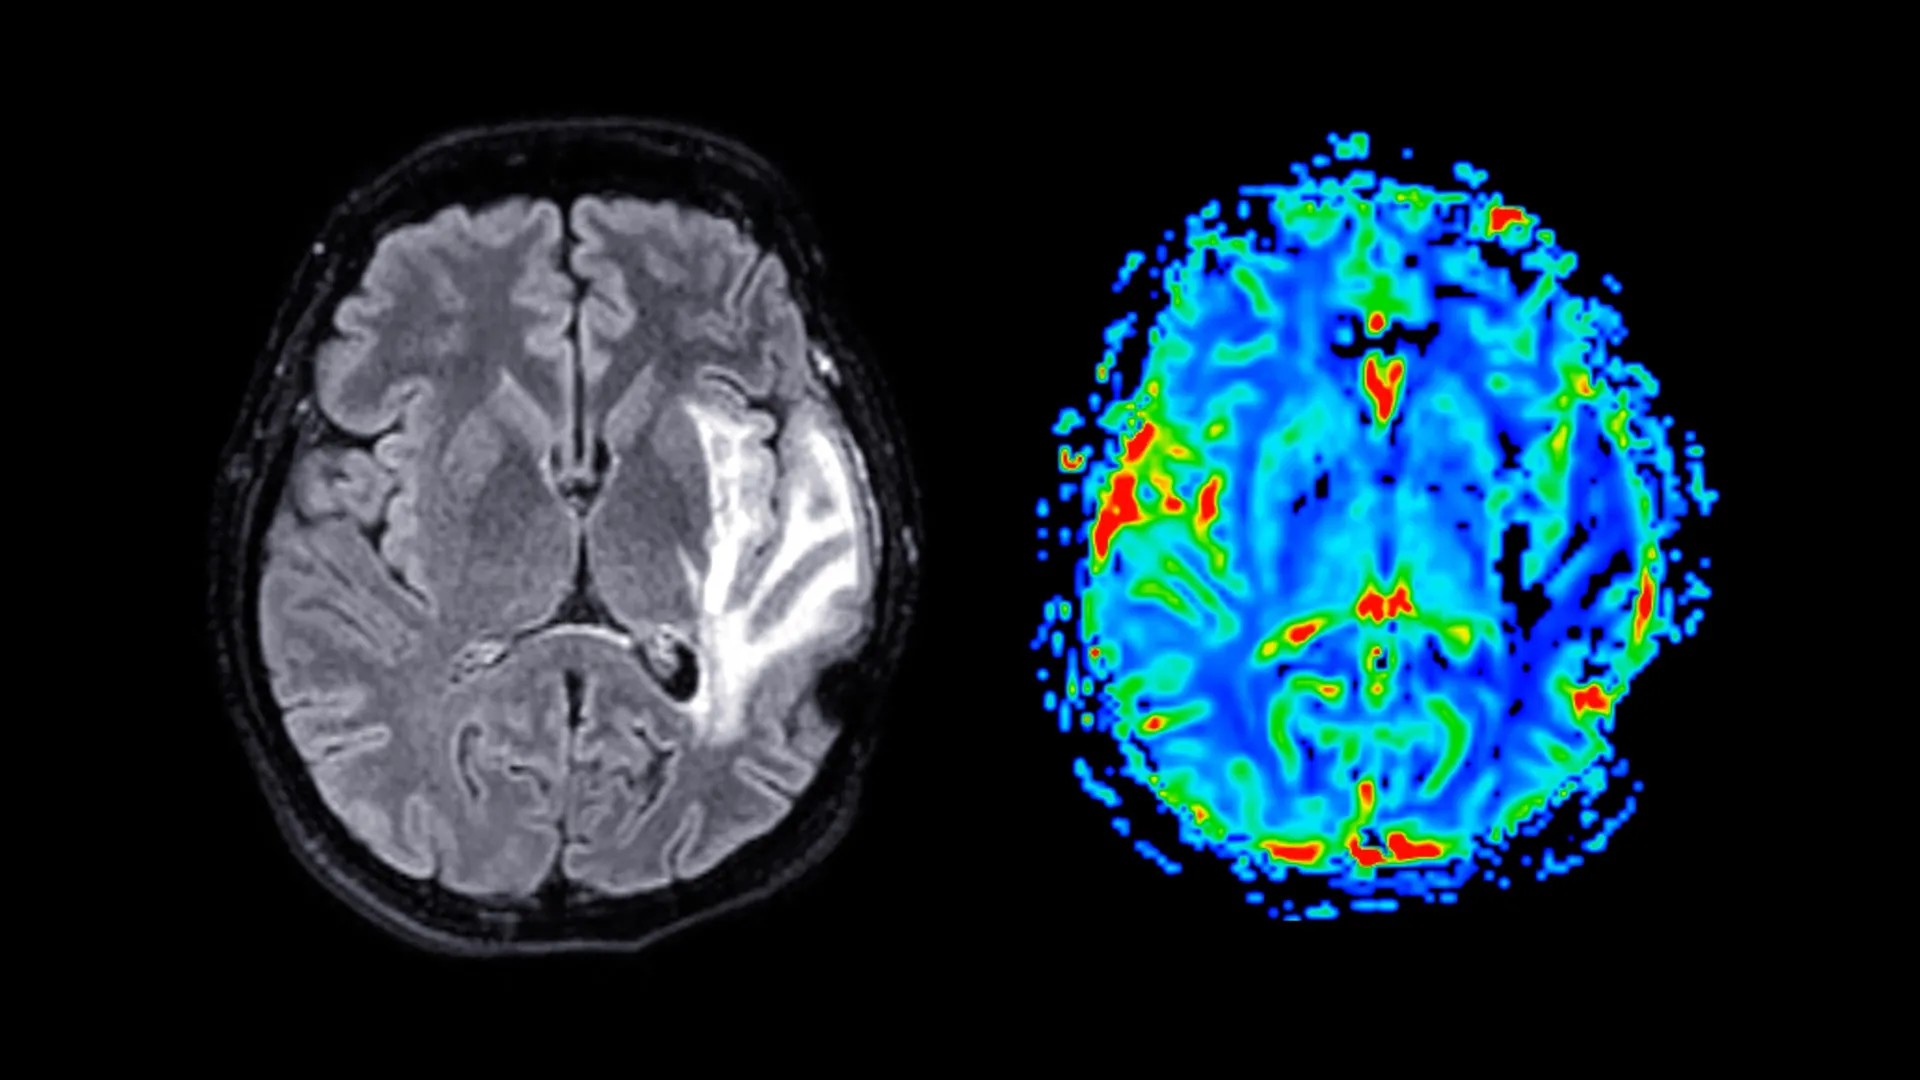

Зміни в структурі мозку

МРТ-сканування показало, що у жінок у постменопаузі зменшився об’єм сірої речовини в гіпокампі (формування пам’яті), енторинальній корі (обробка інформації) і передній поясній корі (емоційна регуляція). Ці області також вразливі до хвороби Альцгеймера, що спонукає дослідників до припущень, що менопауза може збільшити довгостроковий ризик деменції у жінок. Провідний автор дослідження, професор Барбара Саакян, підкреслює, що, хоча це не є остаточним висновком, воно допомагає пояснити, чому у жінок деменцію діагностують майже вдвічі частіше, ніж у чоловіків.